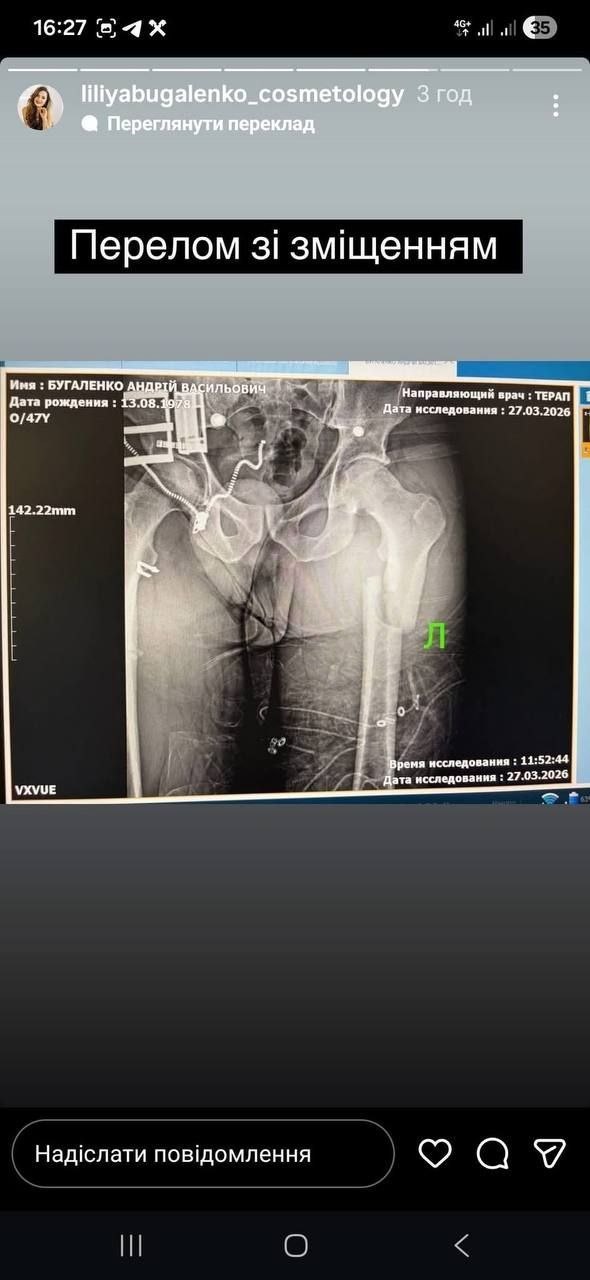

Архаровцев из ТЦК совершенно не интересовало, кто он и есть ли у него документы. По словам пострадавшего Андрея Бугаленко, на улице Левитана на него набросилась толпа в балаклавах, задули его перцовым газом, избили, сломали ногу, а когда увидели, что конечность торчит в сторону под неестественным углом, заставили на камеру сказать, что ногу он сломал сам, а потом просто выбросили из машины на дорогу.